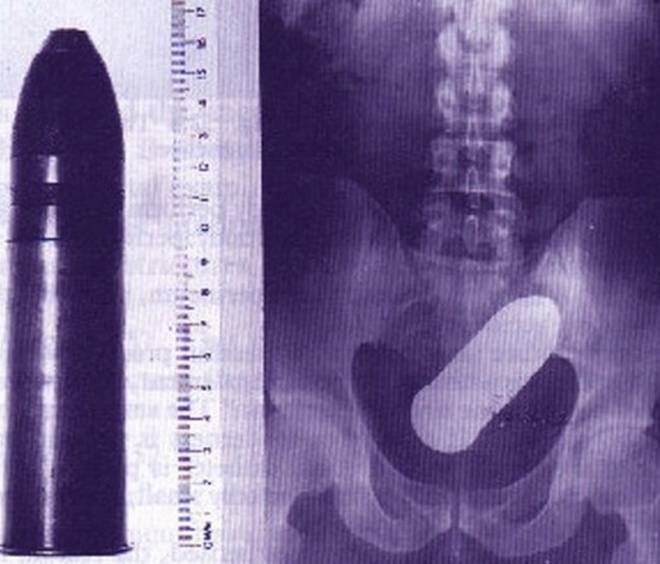

Tutte queste persone sono state ricoverate con diversi oggetti incastrati nell’ano e non solo: dal cellulare alle chiavi di casa, passando per proiettili e giocattoli come macchinine e pupazzetti.